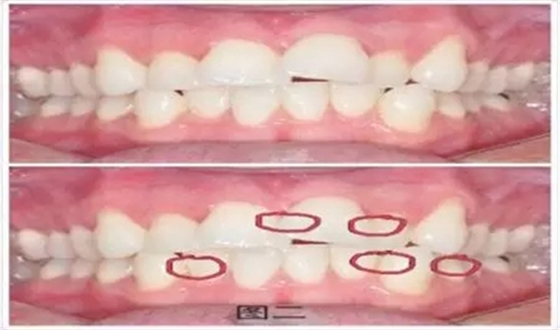

第二種方法是估測(cè)法,即估測(cè)牙齒的擁擠度是否超過標(biāo)準(zhǔn),標(biāo)準(zhǔn)是:上頜或者下頜相鄰的牙是否有重疊,所有重疊的部分相加是否超過了一個(gè)牙的寬度,如果達(dá)到或者超過一個(gè)牙的寬度,建議選擇拔牙矯治。下面以具體圖例為大家解釋說明。

如圖二所示,11 遠(yuǎn)中估測(cè)擁擠度為 1∕6,21 近中和遠(yuǎn)中估測(cè)擁擠度均為 1∕6,這樣上頜的擁擠度加起來并沒有超過 1,即沒有超過一個(gè)牙的寬度,不需要拔牙。下頜同樣。